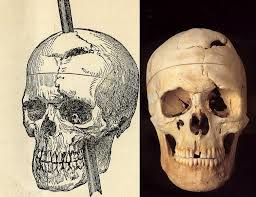

Brain lesion patients

- Lesions in brains or degenerative diseases help us understand brain function

- Phineas Gage– Railroad spike through frontal lobes changed his personality

Furthermore, studies of patients with brain lesions has historically been key to localizing parts of the brain that affect emotional states and learning and memory.

e.g. Phineas Gage in 1848 his whole personality changed after the spike went through his brain.

Harlow wrote: "the equilibrium... between his intellectual faculties and his animal propensities seems to have been destroyed"